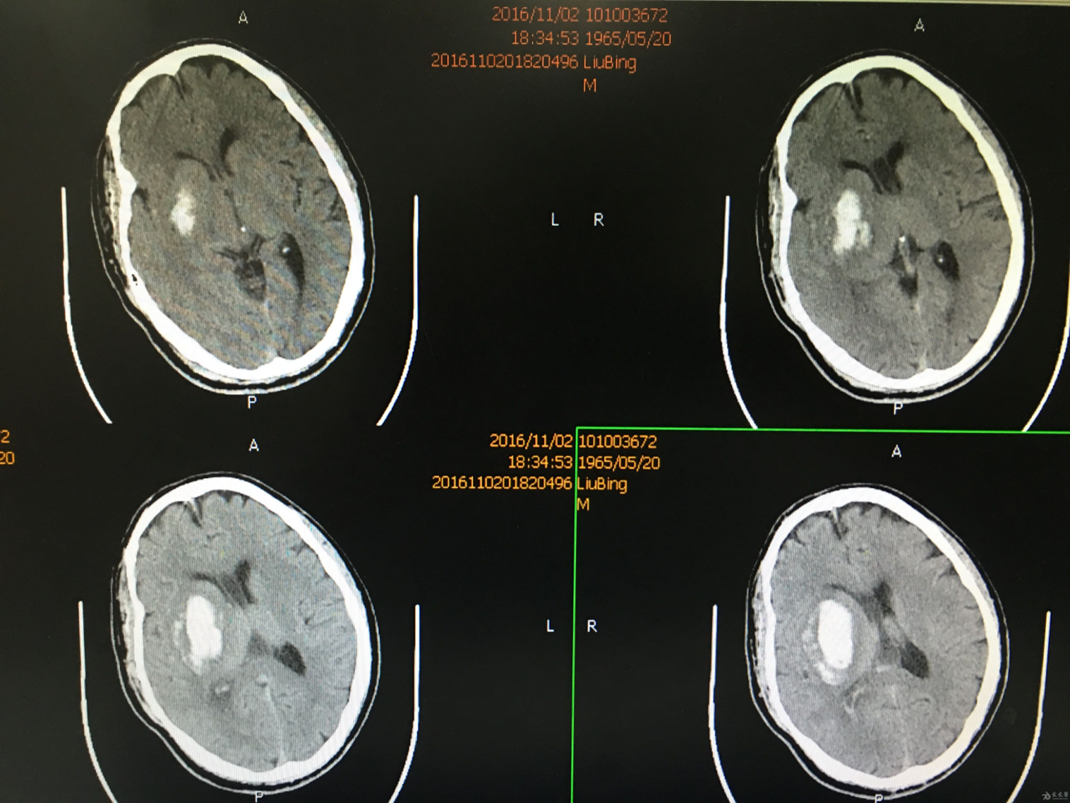

六、到达卒中中心后,会首先通过头颅CT鉴别脑出血及脑梗死。

七、当诊断为脑出血:首要治疗原则:

•保持安静、调控血压、控制出血,根据情况,加强呼吸道管理及护理,预防及防止各种颅内及全身并发症非常重要。

•其中最重要的是血压的管理,因为它是控制出血和再出血的关键点。

•必要时手术治疗。

•脑出血治疗强调一个「早」字,强调早期干预,患者获益越多

八、当头颅CT未见出血,可诊断未脑梗死